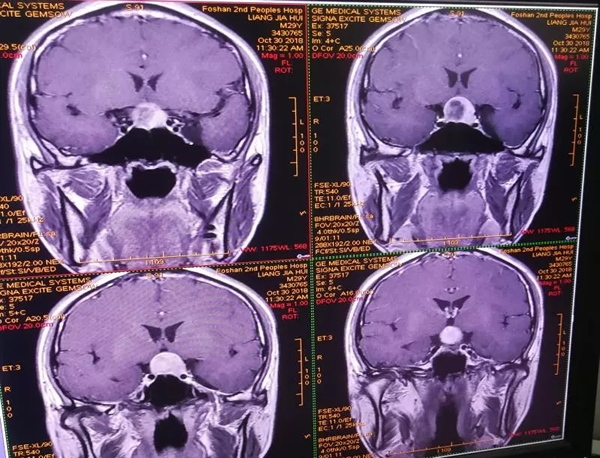

近期,29岁的梁先生因视物不清3个月入住佛山市第二人民医院神经外科。10月31日入院,被诊断垂体瘤。

11月1日,张卫华主任亲自为梁先生切除了垂体瘤;11月2日,梁先生感觉视力明显好转,经评估合乎出院条件准许出院回家。从入院到出院,他共用了3天时间。

张卫华主任介绍,梁先生是市二医院第7例术后第1天出院的患者。垂体瘤切除术后鼻腔免填塞手术是对经鼻垂体瘤切除手术方式的重大且有益的改进,不仅缩短了住院时间,减少了总医疗费用,还明显减轻了患者术后不适。随着梁先生的痊愈出院,也标志着市二医院神经外科的垂体瘤切除术后鼻腔免填塞手术已经进入较为成熟阶段。